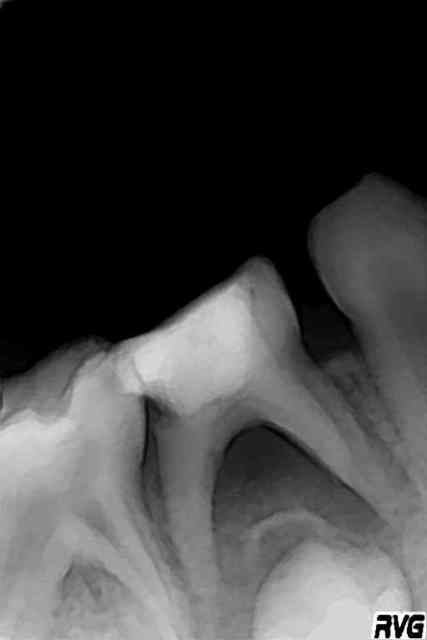

les voila les radios...

84 abces gosse de 6 ans... la question était est-ce qu'on peut garder la dent et comment... souvent qd on a un abces on a une atteinte de furcation.. qui extrait et qui garde?

finalement j'ai laissé ouvert puis obturé à l'hydroxyde de calcium qq jours plus tard...